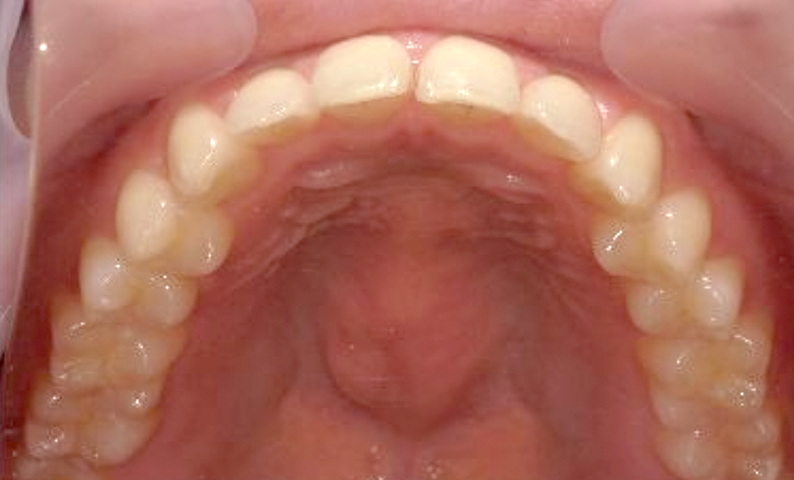

症例:上顎だけの部分矯正

治療期間:7ヶ月金額:24万円+税10代女性すきっ歯上の前歯だけ歯の形態修正